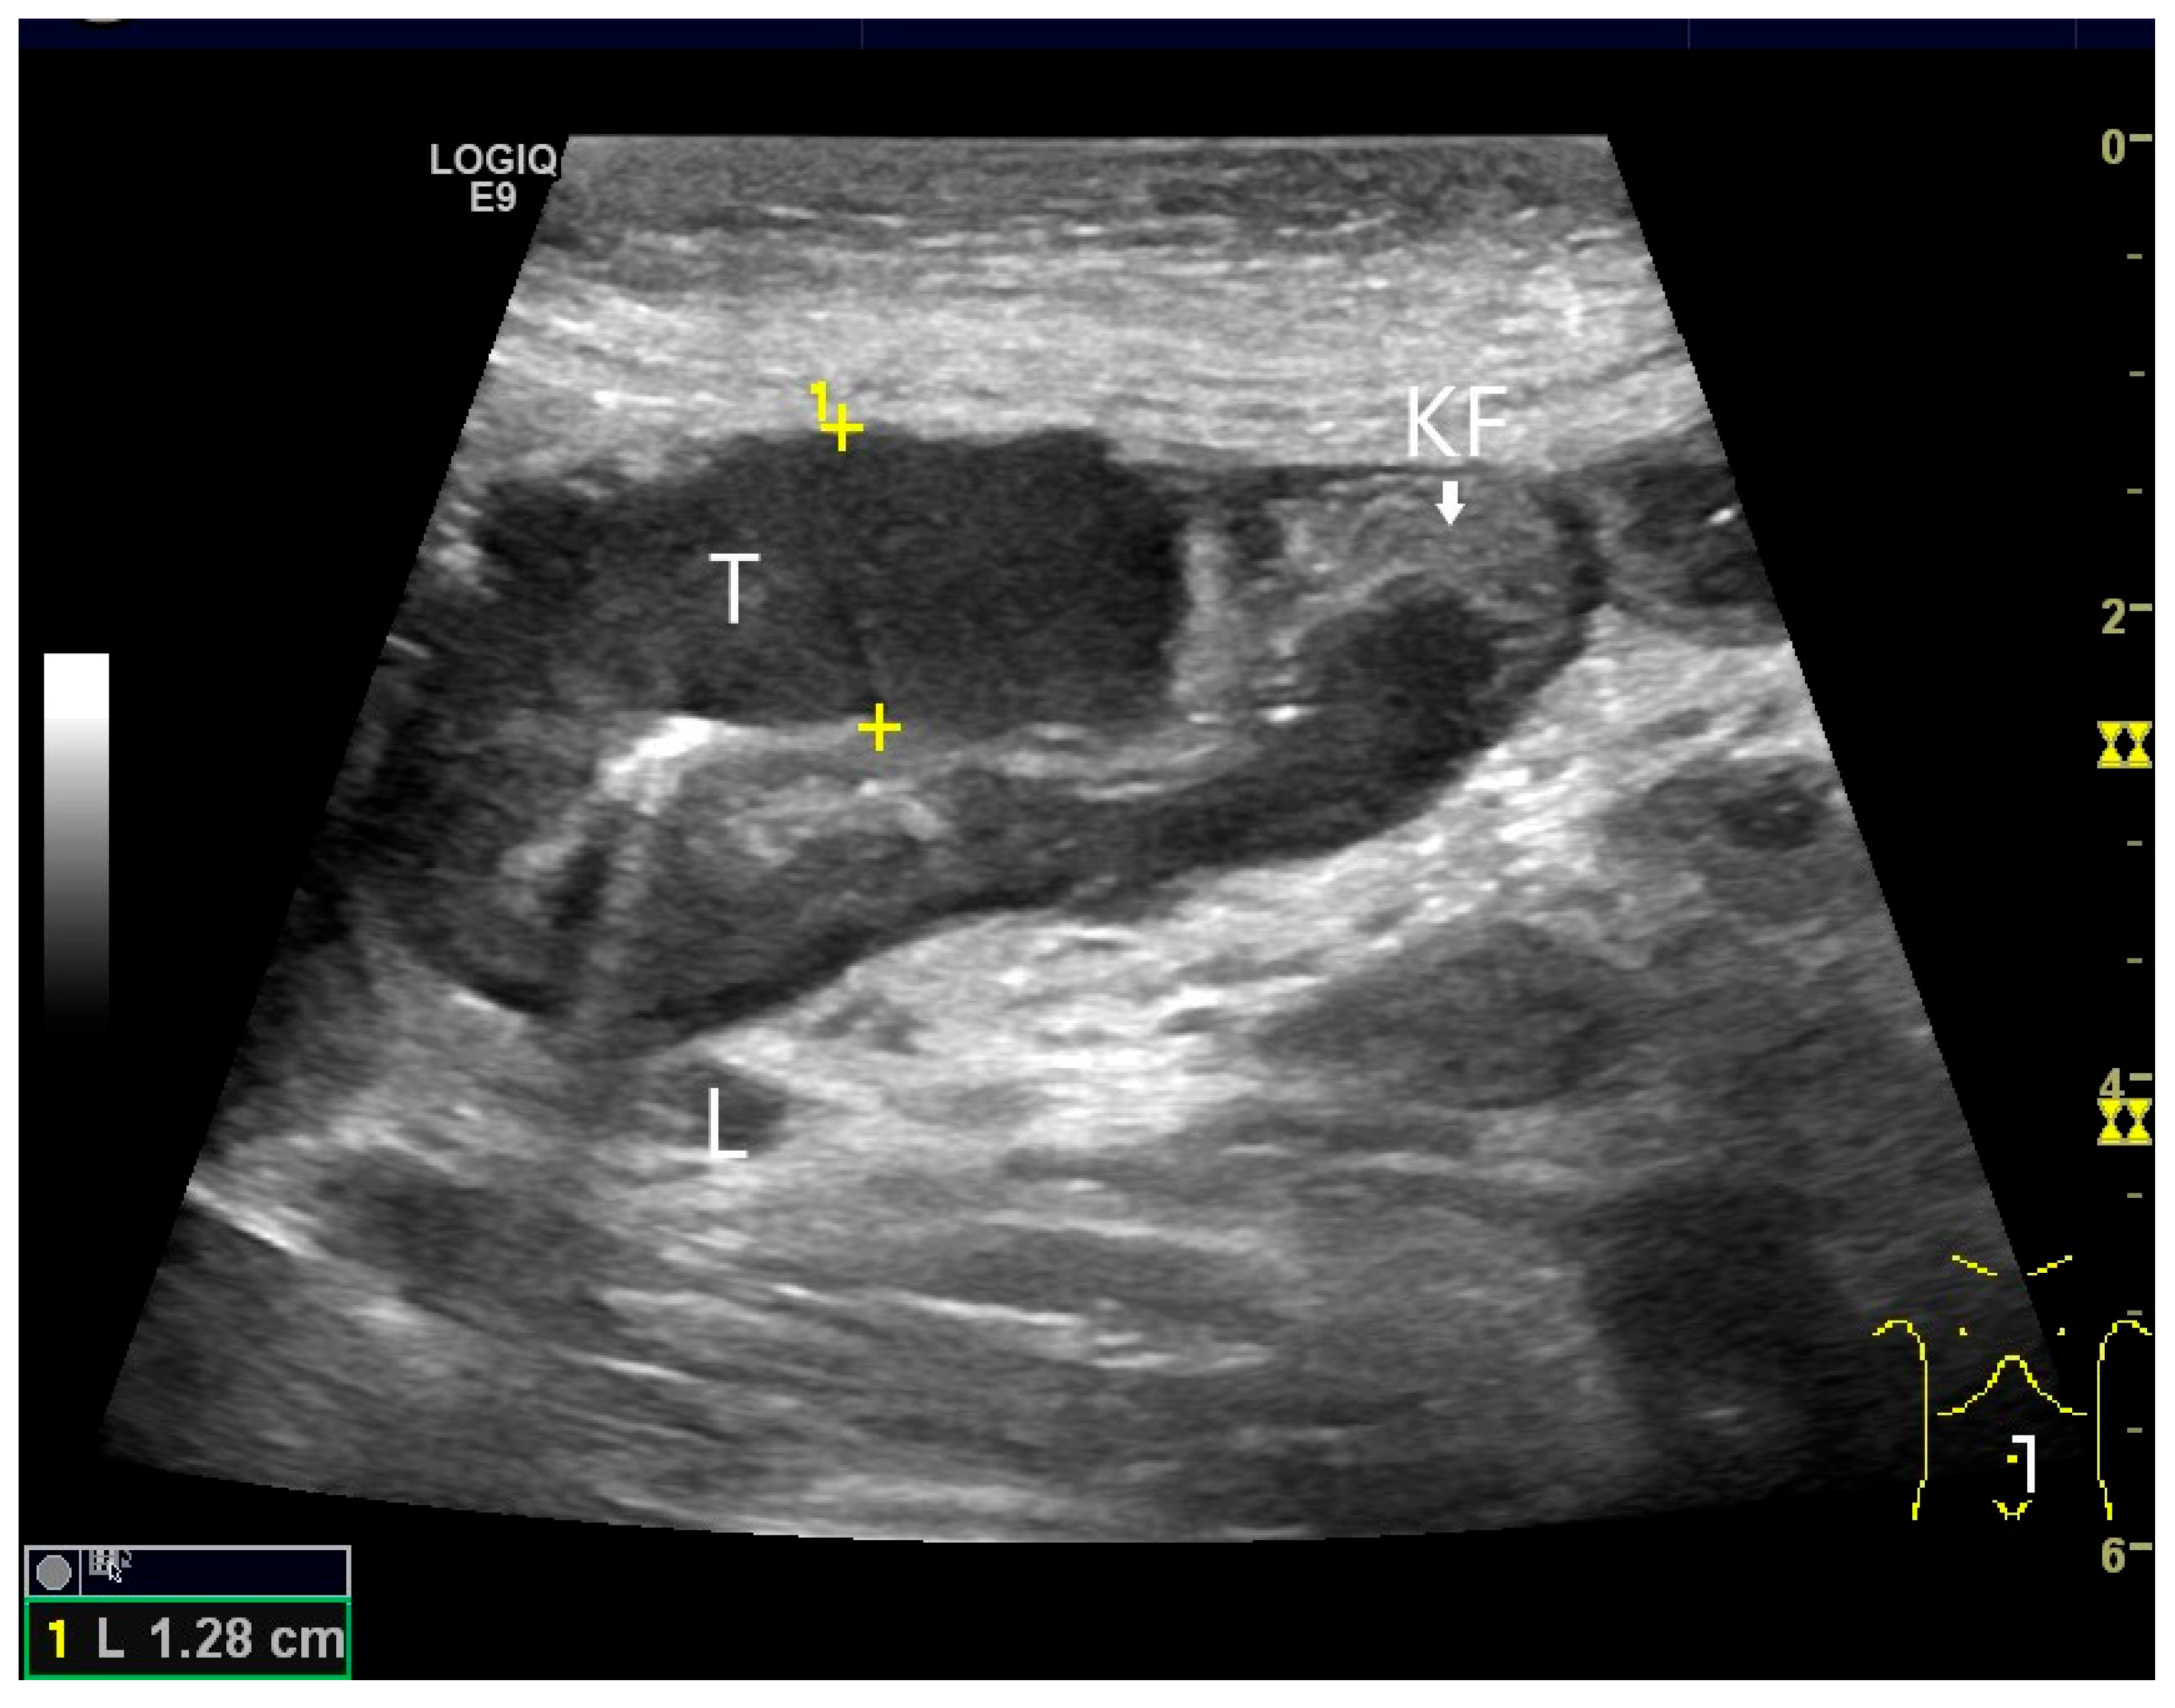

Figure 19.

Small intestine metastasis of pleural mesothelioma. Hypoechoic tumorous wall thickening (T) between the markers. The normal wall with Kerckring’s folds (KF) is visible adjacent to it. Next to the small intestine is a round hypoechoic tumor-suspicious lymph node (L).